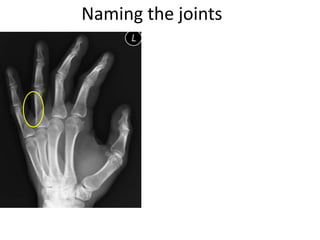

This document provides an overview of hand anatomy including:

- Naming the bones, joints, tendons, nerves and skin landmarks of the hand and wrist.